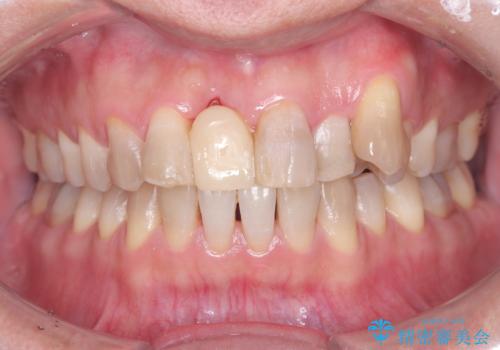

[ 歯周病・矯正・セラミック補綴 ] 歯の総合的なマネージメントを行う包括的歯科治療の実践